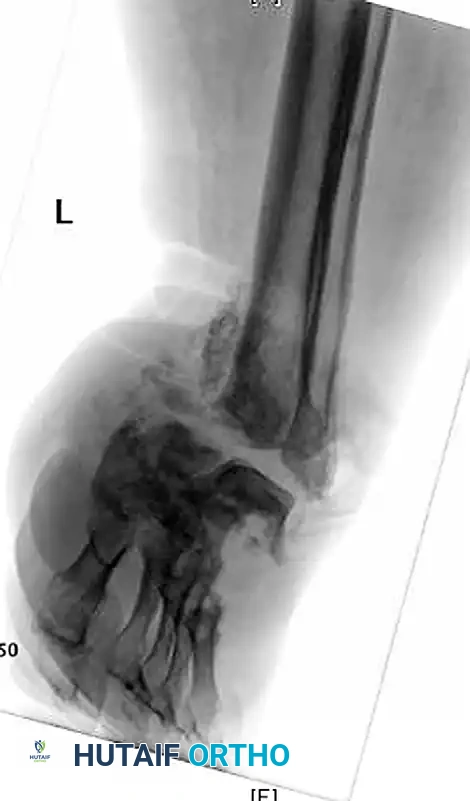

صورة شعاعية توضح انهيار مفاصل ليزفرانك وتشوه القدم

تعتبر الأشعة السينية الأداة الأساسية لتقييم حالة العظام. في المراحل المبكرة، قد تبدو الأشعة السينية طبيعية، ولكن مع تقدم المرض، تظهر علامات تفتت العظام، وخلع المفاصل، وتكون عظام جديدة بشكل غير طبيعي.

توضيح لخلع المفاصل وتفتت العظام في قدم شاركو

صورة تظهر قصر وانحراف العظام في القدم المصابة

أشعة سينية أمامية وجانبية تظهر تدمير المفاصل الرصغية المشطية